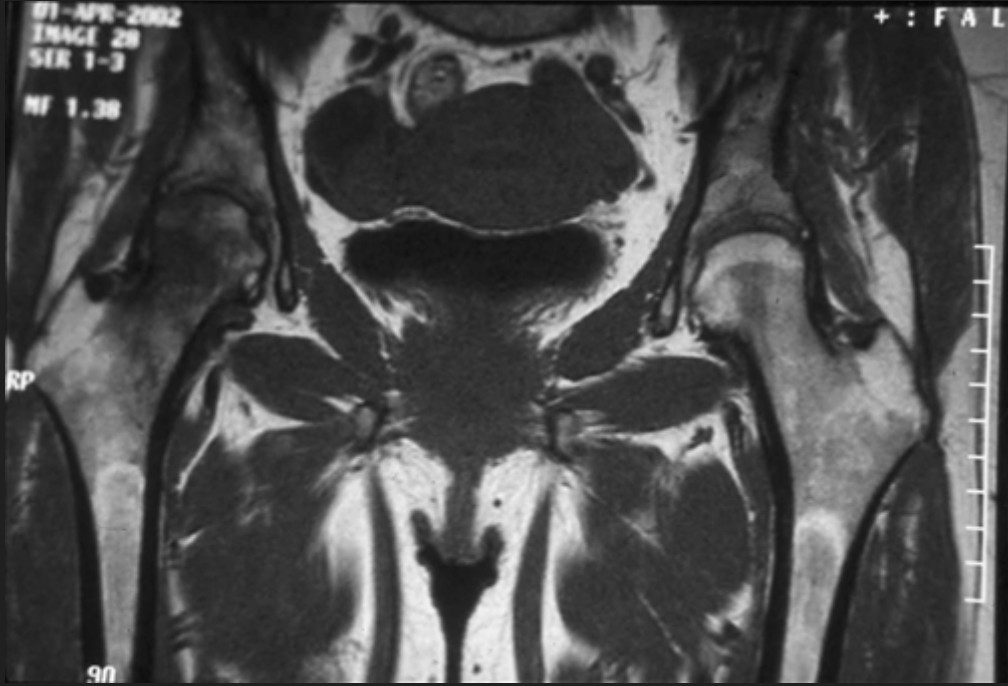

Nekrosis Caput Femoris

Nekrosis caput femoris atau sering disebut dengan avascular nekrosis adalah istilah medis yang digunakan untuk kematian jaringan tulang  di bagian caput femur.